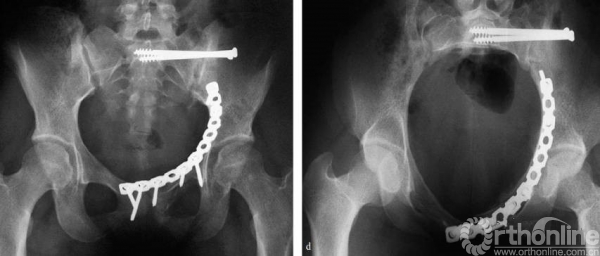

三块钢板

1.上侧钢板与四个关键螺钉

需要沿骨盆缘放置来进行下方骨块的提拉

钢板可用顶棒进行提拉复位,最后可用术中塑形器进行最终塑形。

四个关键螺钉(上一章已经讲过)

1.骶髂关节前处的螺钉;

2.后柱的螺钉;

3.髋臼柱螺钉;

4.耻骨支螺钉。

2.第二块钢板

内侧钢板,该钢板需要过预弯。通过钢板的挤压来复位内移的方形区,沿骨盆缘的内侧进行置放。

当方形区有较大独立骨块的时候,也可以采用T形钢板。

需要注意螺钉不要进入关节

3.第三块钢板、髂坐钢板

来进行后柱的骨折复位,同时可以防止方形区的移位。这三块钢板可单独使用,也可同时使用,根据骨折类型决定。